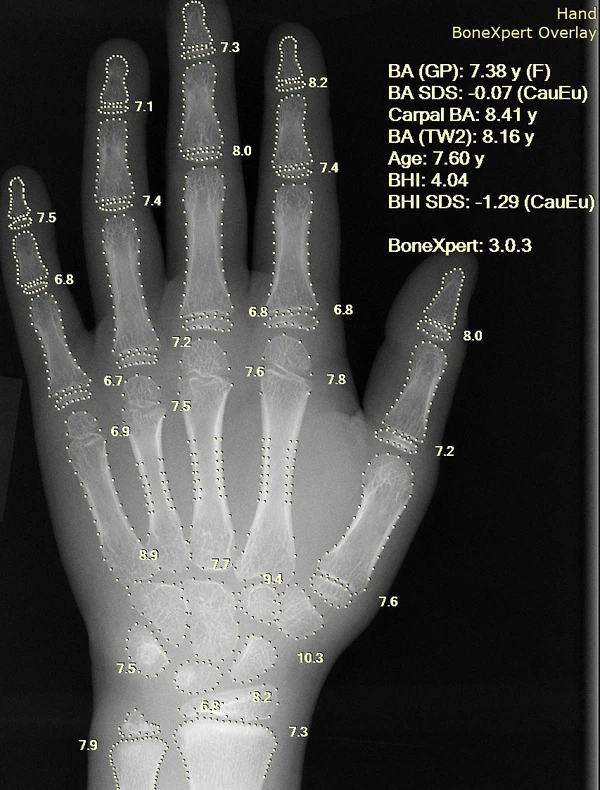

Информатика медицинских изображений и компьютеризация медицинских изображений разрабатывают вычислительные и математические методы для решения проблем, связанных с медицинскими изображениями и их использованием для биомедицинских исследований и клинической помощи. Эти области направлены на извлечение клинически значимой информации или знаний из медицинских изображений и компьютерный анализ изображений. Методы могут быть сгруппированы в несколько широких категорий: сегментация изображений, регистрация изображений, физиологическое моделирование на основе изображений и другие.